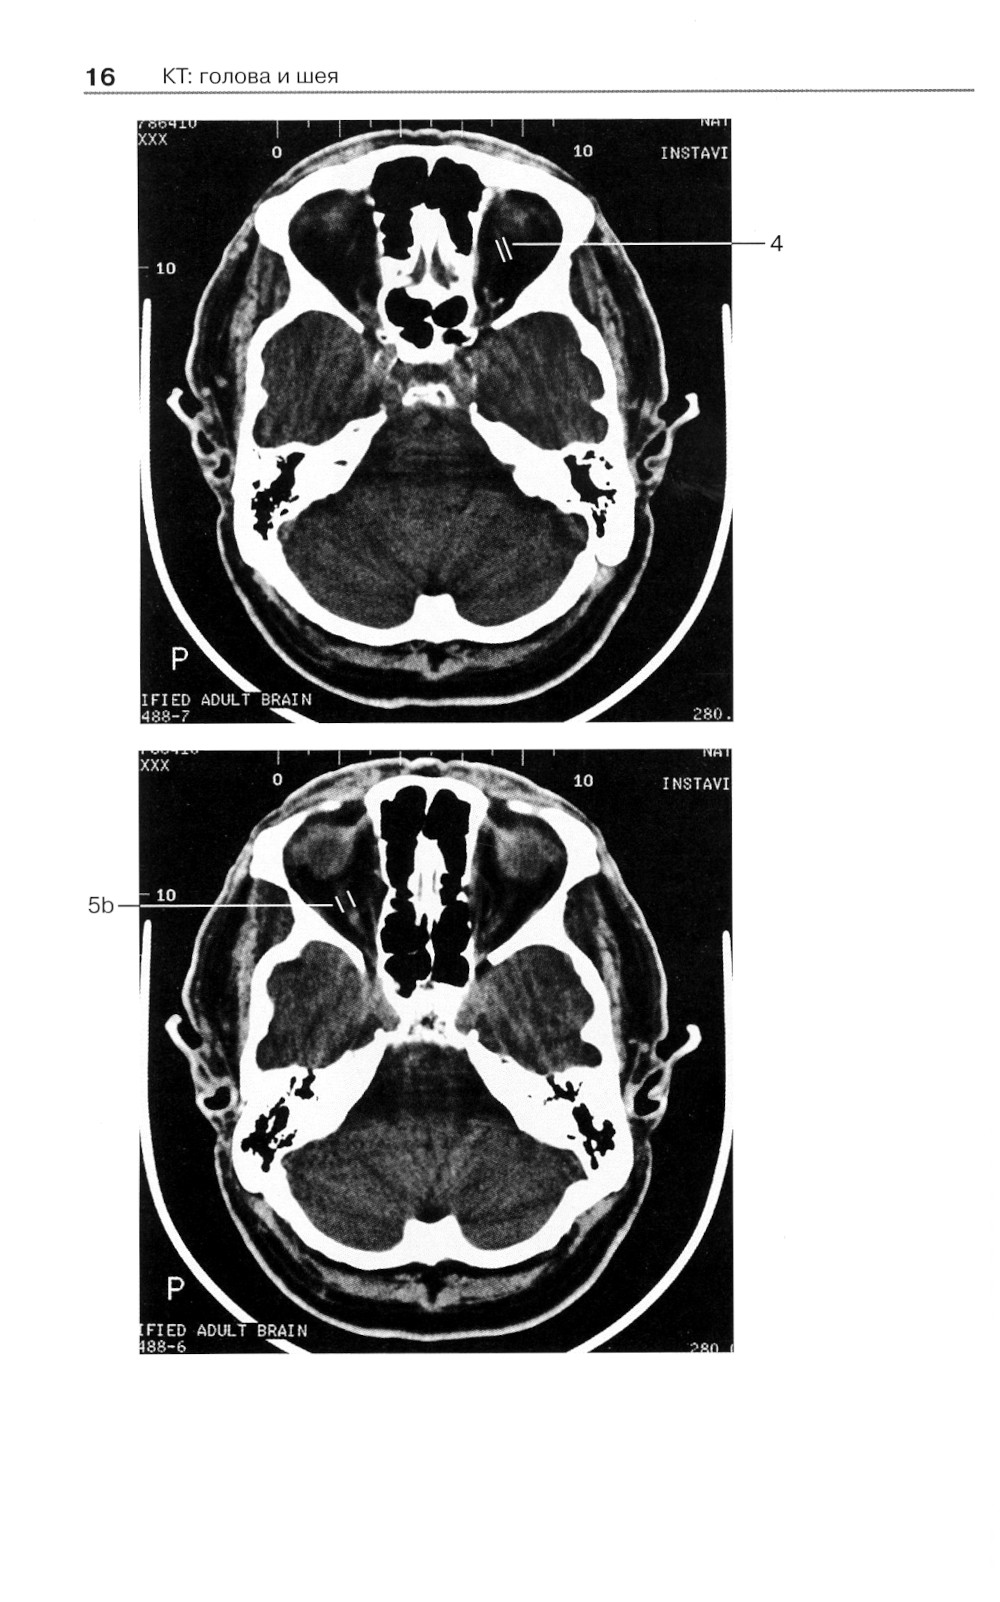

Аннотация: Норма при КТ- и МРТ-исследованиях. 6-е изд

Широкое использование в современной клинической практике компьютерной томографии и магнитно-резонансной томографии как решающих методов диагностики при многих болезнях, относящихся к различным клиническим специальностям и разным анатомическим областям, выдвигает на первый план проблему границ между нормой и патологией при трактовке «изображения на срезах». Помочь врачу - специалисту, составляющему заключение на основании анализа изображений, полученных при КТ- и МРТ-исследованиях, - основная задача этой книги, которая как бы продолжает ранее вышедшую книгу «Норма при рентгенологических исследованиях». Каждому из названных методов посвящен самостоятельный ее раздел, охватывающий все исследуемые анатомические области (голова и шея, грудная клетка и т.д.).| Издательство | МЕДпресс-информ |